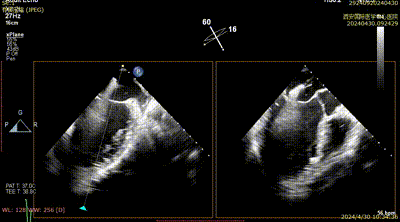

Case 2影像资料

房间隔穿刺

导引鞘系统植入

二尖瓣夹系统瓣上调整

二尖瓣夹系统进入左室

二尖瓣夹捕获瓣叶

二尖瓣夹夹闭

术后二尖瓣反流评估

术后结果